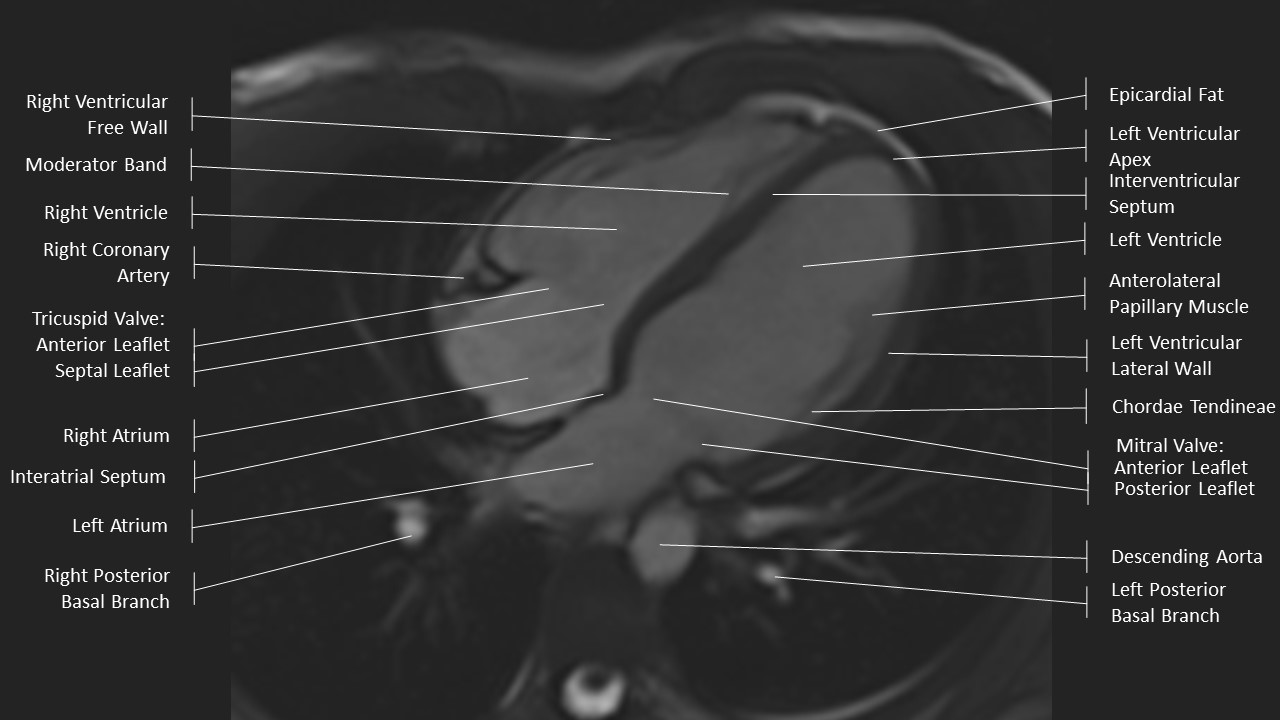

4 Chamber View